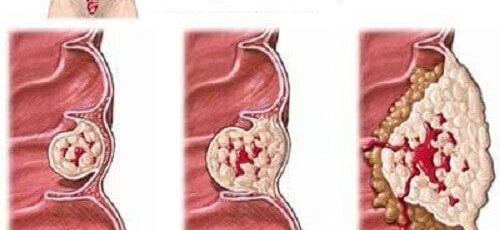

대장이라는 기관은 우리 몸 소화기관의 마지막에 있는 부위인데요 길이는 1.5m가량 되며, 소장 다음으로 길이가 긴 장기로 대변이 만들어지는 최종 마지막 장기입니다. 암이 결장에 생기면 결장암, 직장에 생기면 직장암이라고 하는데요 이를 통상적으로 대장암이라고 합니다. 즉 대장암이란 결장이나 직장에 생기는 악성 종양으로 대부분이 점막의 샘 세포에 생기는 경우입니다.

대장암 초기증상을 느껴서 병원에 갔을때 이미 대장암이 많이 진행된 경우가 대부분이라고 합니다. 하지만 초기인 1기의 경우라면 내시경 치료만으로도 치료가 가능할수 있다고 하나, 더 발전된 2기,3기 상태라면 현대 의학으로는 비수술치료로 대장암을 낫게 할수는 없다고 합니다. 유일한 치료방법은 수술이라고 할 수 있습니다. 대장암이 발견된 부위를 포함하여 대장을 제거하고 주변 임파선과 혈관들을 동시에 제거해주는 수술법인 '근치적 절제술'이 대장암 수술중 가장 기본이 되는 방법입니다. 수술을 하고나서는 암 기수에 따라서 항암치료를 병행하면서 경과를 지켜보게 돼요.